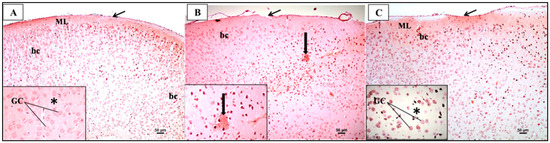

In the control group (Figure 11A,B), the examination of H&E sections of the PFC revealed a normal structure in the form of six successive layers from the outside to the inside: the outer molecular layer (ML), external granular layer (EGL), external pyramidal layer (EPL), internal granular layer (IGL), internal pyramidal layer (IPL), and polymorphic layer (PL). The higher magnification of these layers showed that the outer molecular layer under the pia mater mainly contained the dendrites of underlying cells with some neuroglial cells. The other layers were formed mostly of mixed pyramidal and granular cells. The pyramidal cells appeared triangular with large vesicular nuclei, while the granular cells appeared rounded with large vesicular nuclei. The background or neuropil appeared pinkish and contained some blood vessels and neuroglial cells. In contrast, the examination of the H&E-stained sections of the PFC from the LPS group (Figure 11C,D) exhibited disturbed layers and the cellular distribution of neurons with increased darker neurons as compared with the control group. Most of the pyramidal and granular cells appeared condensed and deeply stained. There were also more neuroglial cells and congested capillaries. On the other hand, the examination of H&E sections of the prefrontal cortex from the treated group (Figure 11E,F) showed a restoration of the normal arrangement and cellular distribution of neurons when compared to the LPS group. Most of the pyramidal and granular cells appeared normal in shape with a few cells that were shrunken and deeply stained. There were also fewer neuroglial cells and fewer congested capillaries.

Figure 11.

Representative photomicrographs of H&E-stained sections of the prefrontal cortex (PFC) from mice in the different groups. (A) Normally organized layers of the prefrontal cortex from superficial to deep: molecular (ML), external granular (EGL), external pyramidal (EPL), internal granular (IGL), internal pyramidal (IPL), and polymorphic (PL) layers. Arrow = regularly attached pia mater (H&E × 100). (B) A higher magnification of the upper part of the PFC displaying ML, EGL, and EPL reveals the appearance of granular cells (GC) and pyramidal cells (PC). Neuroglial cells (Ng) and blood capillaries (bc) within the acidophilic neuropil (*) can also be identified. (C) Irregularly attached pia mater (arrow) and the disturbed layers and cellular distribution of neurons of the PFC. (D) A higher magnification of the upper part of the PFC displaying ML, EGL, and EPL reveals more disturbed layers and cell distribution compared to the control group. Notice that most of the pyramidal and granular cells appear condensed and deeply stained. There were also more neuroglial cells (Ng) and congested capillaries (bc). (E) Regularly attached pia mater (arrow) and slightly arranged layers of the PFC that are bordered by white matter (wm). (F) A higher magnification of the upper part of the PFC displayed many apparently normal neurons, with a few cells appearing condensed together with apparently normal blood capillaries (bc) (H&E × 200). * refers to the background or neuropil that appeared pinkish and contained blood capillaries and neuroglial cells.